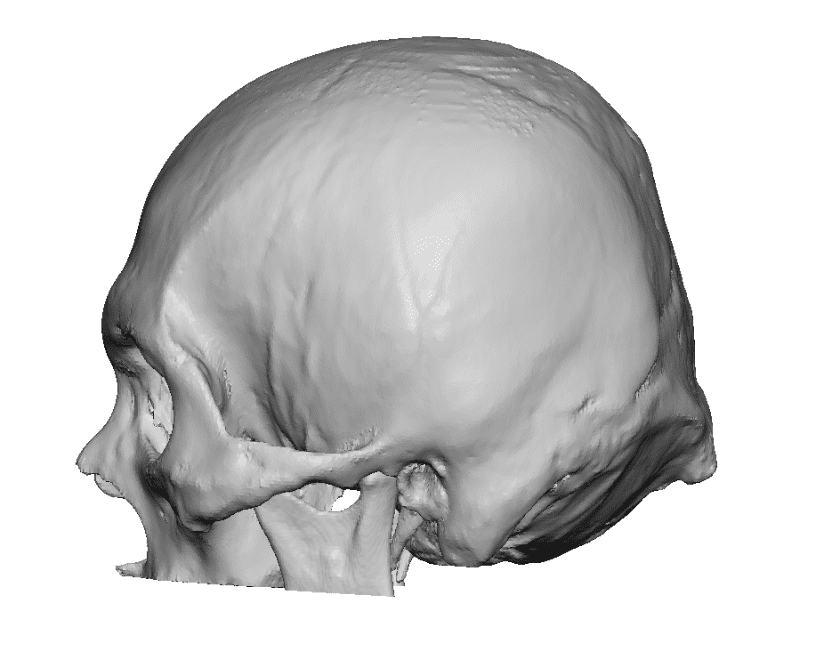

Patient 100

Desire for reshaping of an asymmetric flat back of the head in a shaved head male.

A combined back of the head reshaping procedure was done with a custom skull implant, sagittal ridge reduction and a right temporal muscle reduction.